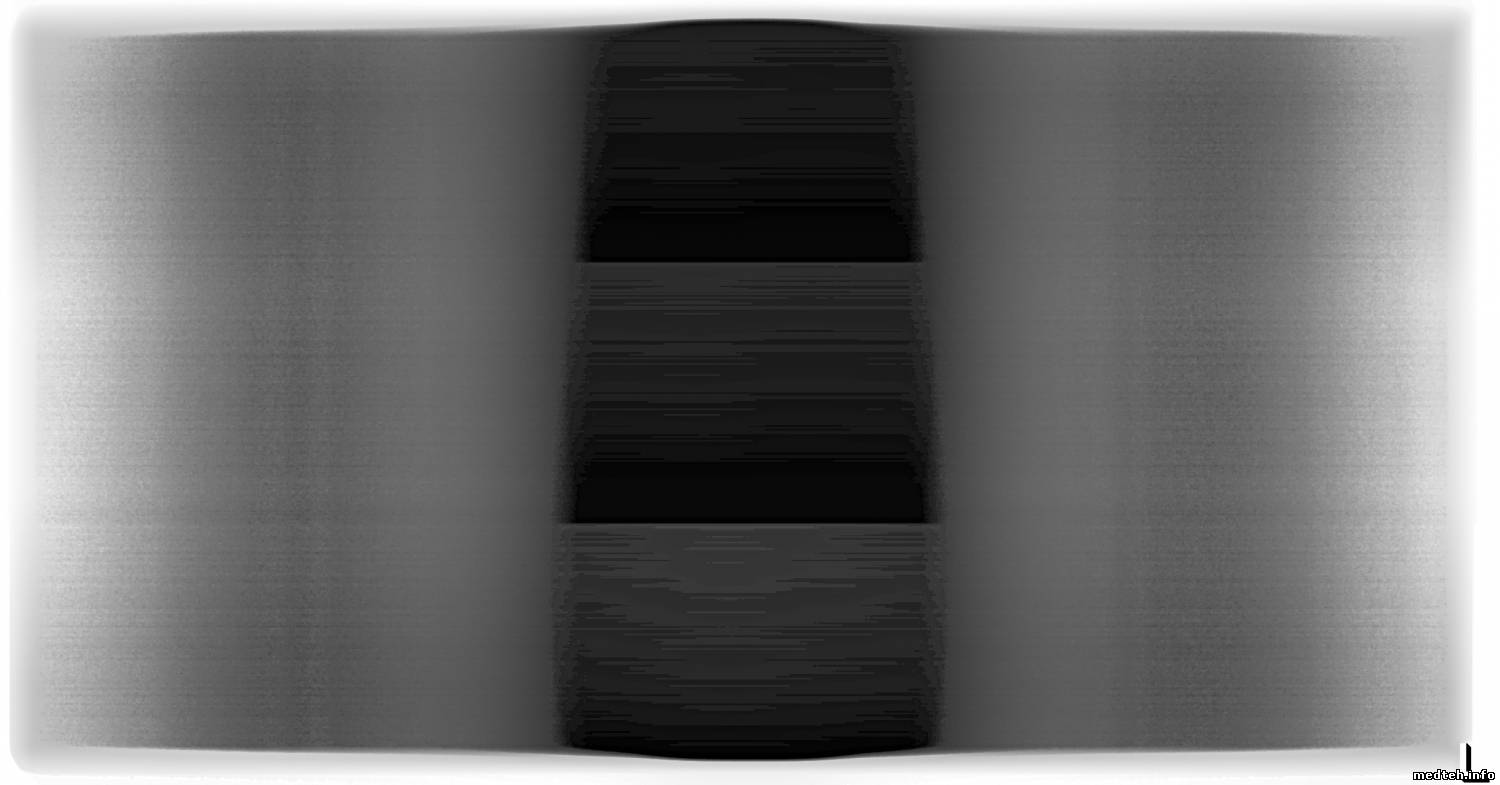

Геометрические искажения, там калибруються тоже программно, а вот горизонтальные полосы на снимке, ума не приложу, как убрать. Несколько снимков во вложении. На середине снимка хорошо видно 3-и приёмника (детектора). Чем дальше,тем хуже. Чётче видны горизонтальные полосы.